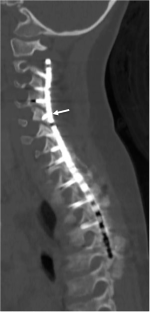

We identified 5 patients with the mean age of 4.4 years (range 2–6 years) who all had spinal cord injury with subluxation or dislocation at C6–7. All patients underwent posterior cervico-thoracic fixation with mandibular instrumentation from C2 to the upper thoracic spine. There was one complication of a right vertebral artery occlusion by screw placement, which did not cause harm. Suboptimal screw placement was detected in 18.4% of screws, but no revision was needed, since it was asymptomatic. All patients fused successfully without significant hardware failure. The mean time of follow up was 91 months ranging from 33–187 months.

Mandibular screw and plate fixation was effective to treat the acutely traumatic unstable subaxial cervical spine in the young pediatric population. The rate of suboptimal screw placement may be reduced by placing shorter screws into the lamina, pedicles, or facets if the plate hole does not align for a standard trajectory needed for lateral mass or pedicle screw placement.